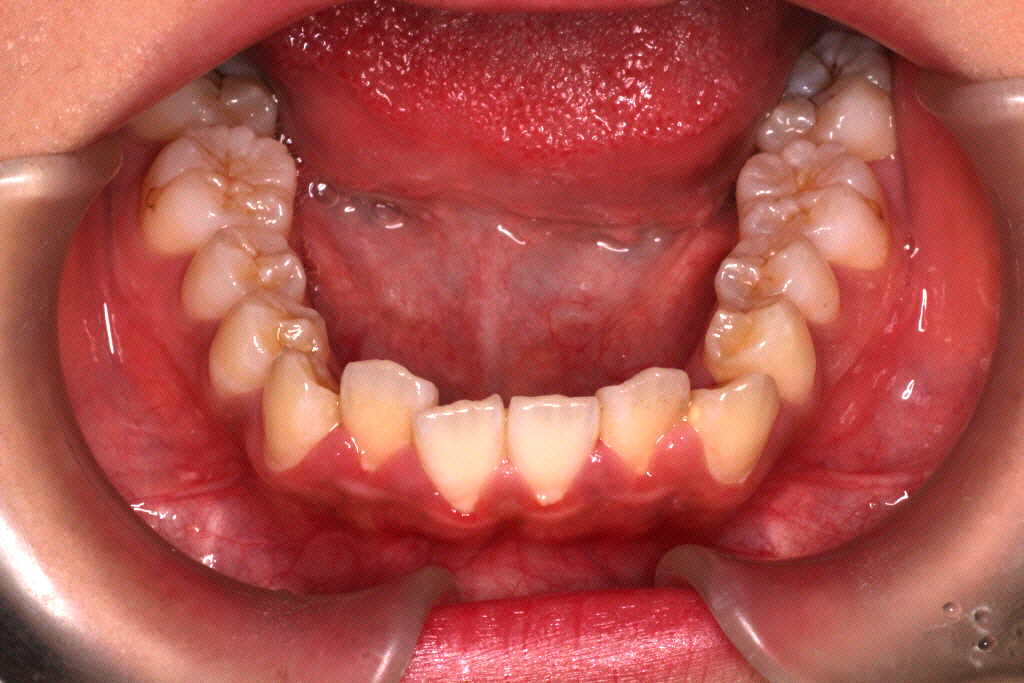

上下マウスピース19枚を1週間ずつ使い、5ヶ月後のお口の中の状態です。↓

●改善点の結果

①ねじれもすっかりきれいになりました。

これでこの方は矯正期間約3年で歯列矯正が終わりました。

カリエールモーションを装着していた時にゴムかけができていれば、もう少し期間を短くできたケースですね。